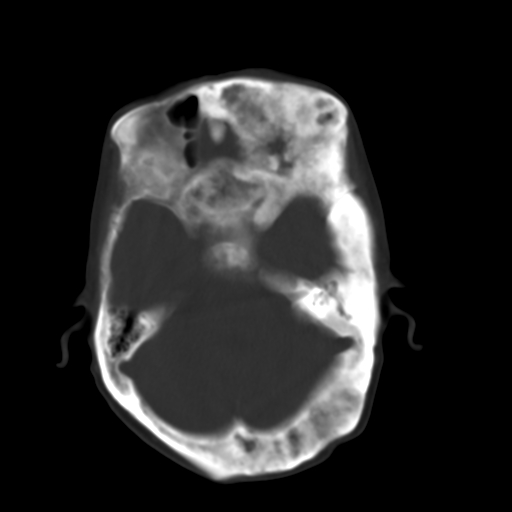

标题: CT17003:F58Y,骨纤维异常增殖征 [打印本页]

标题: CT17003:F58Y,骨纤维异常增殖征

女58y 头晕就诊

左侧额骨增厚,板障层密度增高。 支持骨纤维异常增殖症  。

符合颅骨骨纤维异常增殖症表现。